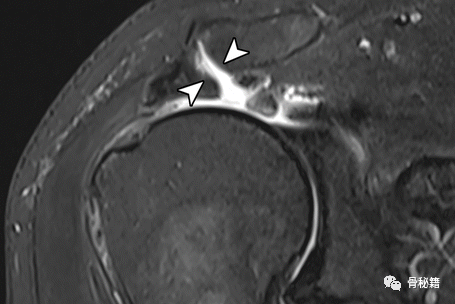

男性喙突韧带的正常解剖结构。右肩浅斜冠状 T1 加权 MR 关节造影显示正常韧带起源于喙突。喙肩韧带(弯曲的箭头)位于最外侧,以浅角度向肩峰延伸。在喙肩韧带内侧,CC韧带的梯形部分(箭头)插入锁骨外侧的下缘。锥形韧带(直箭头)位于梯形的后内侧,具有垂直方向的纤维,连接到距关节一定距离的锁骨下后缘。